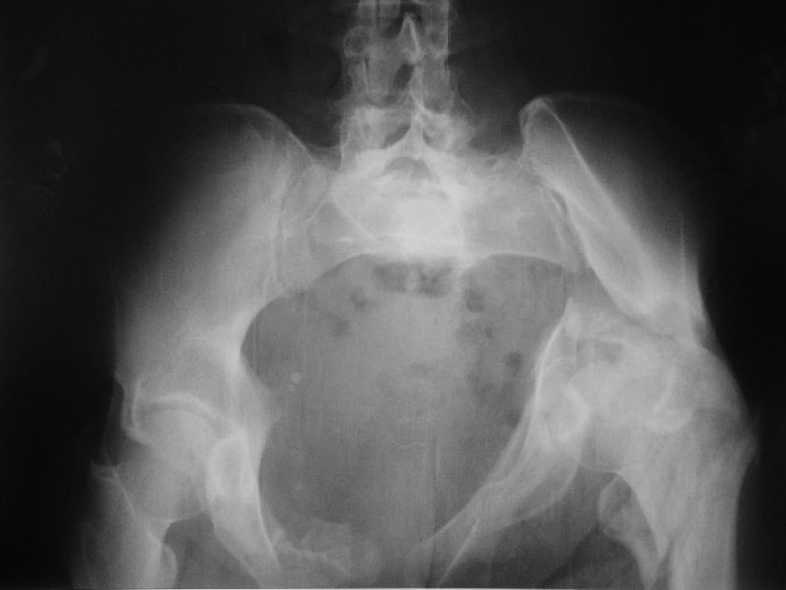

Больная 43 года (промышленный альпинист), 28.07.08 в результате падения с 5 этажа получила политравму:

Перелом свода и основания черепа. Вертикально-нестабильное повреждение таза, осложнённое разрывом мочевого пузыря. Чрезвертельный перелом левого бедра. Перелом правой таранной кости, переломовывих правой кубовидной кости. Тупая травма живота, разрыв печени, ушиб почек. Забрюшинная гематома. В день травмы - лапаротомия, ушивание ран печени. Разрыв мочевого пузыря не диагностирован. Течение болезни осложнилось развитием мочевого затёка и обширной пред- и забрюшинной флегмоны, сформировался свищ мочевого пузыря. 19.8.2008 вскрытие, дренировние флегмоны, ревизия мочевого пузыря, обтурация мочевого свища (свищ закрылся в октябре), 1.10.2008 некрэктомия, пластика по Шеде-Лидскому правой кубовидной кости. По результатам КТ диагностирован рак правой почки (диагностическая находка), 8.10.2008 нефрэктомия справа.

Имеется вертикальное смещение левой половины таза с выраженным отведением крыла (клинически подвижности нет), несросшийся низкий двухколонный перелом левой вертлужной впадины с потерей конгруэнтности, укорочение около5 см, застарелый разрыв лонного сочленения, неправильно сросшиеся переломы обеих ветвей правой лонной кости с укорочением, патологическая подвижность лоно-седалищного фрагмента слева. Правая нижняя конечность неопорна, несмотря на то, что лежа прямую ногу поднимает, ходит на левой ноге (ортопедическая обувь) с костылями, справа тазобедренный ортез. Седалищные нервы работают.Урологи отпустили больную на 6 мес.